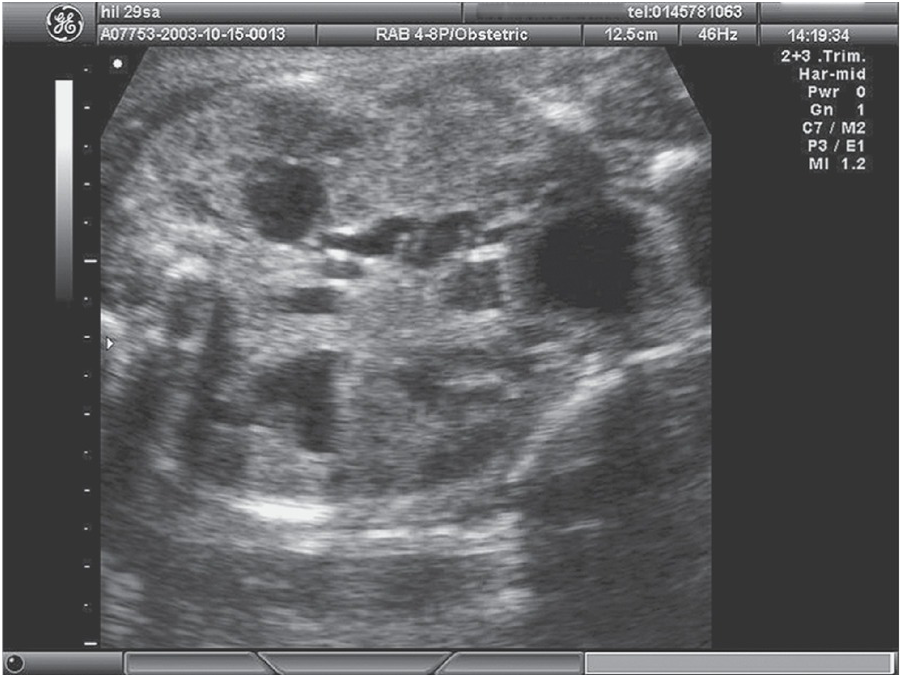

Dating scan (12-week scan , booking scan or due date scan ) At 12 weeks you will be able to see more detail and make out hands and feet . With a few exceptions from 10 weeks of pregnancy, you would normally have an abdominal ultrasound .

Early, dating and viability scans (6 - 15 weeks) Why have an early pregnancy scan ? . . . How is the scan carried out? Under 10 weeks the best way to see your baby and get clearer images is by carrying out a transvaginal scan (internal scan ) . However, if you would prefer to come with a full bladder we can start by scanning you this way and the . . .